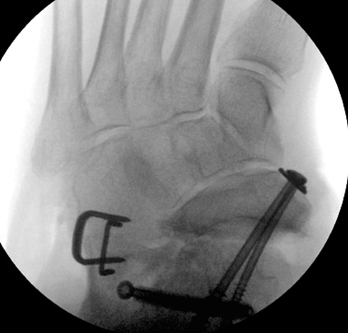

TOTAL ANKLE REPLACEMENT :: ORIF CALCANEUS :: ORIF ANKLE FRACTURE DISLOCATION :: COMPLEX BUNION AND LESSER TOE CORRECTION :: TALUS FRACTURE -1 :: TALUS FRACTURE -2 :: LISFRANC REPAIR :: COMPLEX TRIPLE ARTHRODESIS 1 :: COMPLEX TRIPLE ARTHRODESIS 2 :: MINIMALLY INVASIVE BUNION REPAIR 1 :: MINIMALLY INVASIVE BUNION REPAIR 2 :: ARTHROSCOPIC CARTILAGE REPAIR :: TENEX SPUR DEBRIDEMENT :: Haglunds Debridement and Achilles Repair